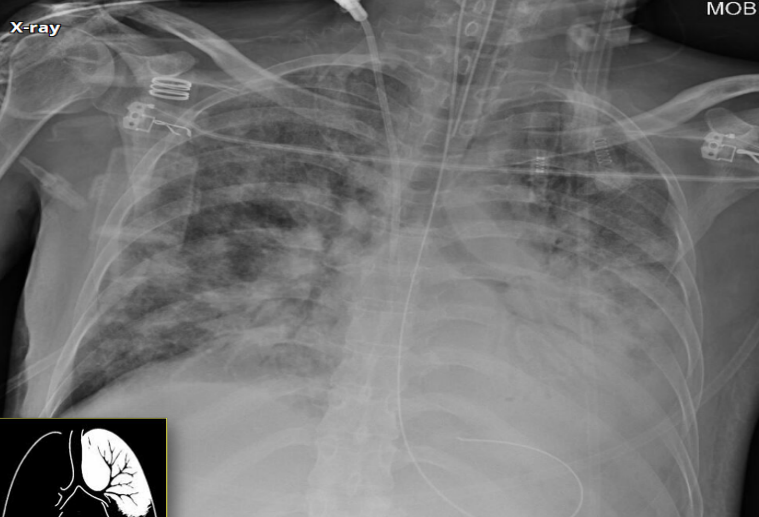

AP chest X-ray

Opacity on right side

Grading sign (indicates pleural effusion in AP view)